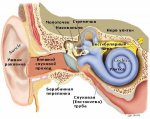

Тубоотит (евстахиит)Евстахиева (барабанно-глоточная) труба соединяет носоглотку с барабанной полостью. Евстахиева труба выполняет... Тубоотит (евстахиит)Евстахиева (барабанно-глоточная) труба соединяет носоглотку с барабанной полостью. Евстахиева труба выполняет...